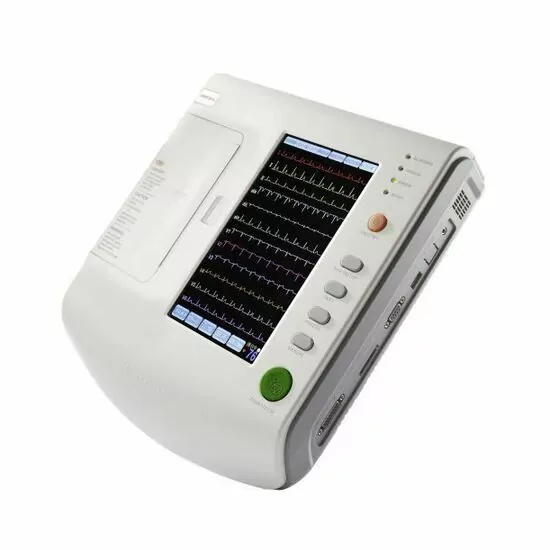

ECG MACHINE 6 CHANNEL - MEDEXBIO

ECG MACHINE 6 CHANNEL - MEDEXBIO

Digital 6 Channel ECG Machine

Digital 6 Channel ECG Machine

Edan ECG Machine SE-601 Series 6-Channel ECG

Edan ECG Machine SE-601 Series 6-Channel ECG

CONTEC ECG600G Digital 6 channel Electrocardiograph ECG machine EKG CE

CONTEC ECG600G Digital 6 channel Electrocardiograph ECG machine EKG CE

Dawei ECG Machine 3 Channel

Dawei ECG Machine 3 Channel